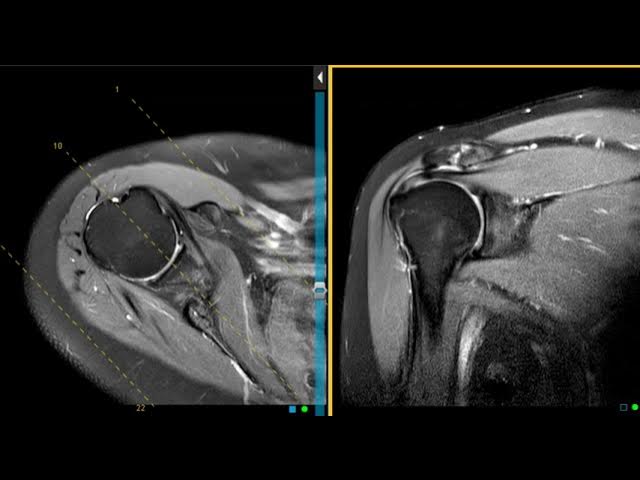

Your rotator cuff isn't one thing. It's a group of four muscles and their tendons that work together to stabilize your shoulder joint. Think of it like a muscular cuff surrounding the ball-and-socket joint of your shoulder, keeping the upper arm bone (humerus) centered in the socket (glenoid).

The four muscles are the supraspinatus, infraspinatus, teres minor, and subscapularis. When they work properly, you can rotate your arm, lift it overhead, and perform thousands of movements without thinking about it. When something goes wrong, you feel it immediately.

Over decades of use, these tendons develop changes. Microtears occur. Fibers fray. The tissue develops small defects. In the language of radiology, these become "abnormalities."

But here's where the disconnect happens. The radiologist describes these changes precisely because they're trained to report everything they see. That's their job. But "abnormal" in the imaging sense doesn't equal "abnormal" in the clinical sense—meaning it doesn't automatically mean something is wrong with how your shoulder functions.